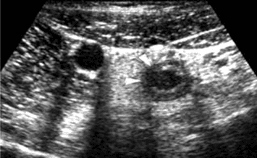

Los hallazgos ecográficos de apendicitis aguda incluyen:

·

Diámetro transverso mayor a 6 mm: Este parámetro tiene una sensibilidad del 98 % (Sivit, 2001). Sin embargo, hasta el 23 % de los pacientes adultos sanos tienen un apéndice cecal con un diámetro transverso mayor a esta medida. Es por eso por lo que algunos autores proponen que al encontrar un apéndice con un diámetro entre 6 y 9 mm debe considerarse ‘indeterminado’ y deben buscarse otros signos de apendicitis; tales como la no compresibilidad, la forma y la alteración de la ecogenicidad de los tejidos adyacentes ((Rybkin, 2007. Brown, 2008).

Figura. Apendicitis aguda, apariencia en ultrasonido. a) Imagen axial del apéndice cecal sin compresión, en la cual se ve engrosada (calipers), con un diámetro de 13 mm. b) El diámetro del apéndice no se modifica con las maniobras de compresión. Igualmente, se observa una alteración en la ecogenicidad de la grasa adyacente que no es compresible (*).

· Apéndice no compresible: El apéndice normal debe ser móvil y compresible. La pérdida de la compresibilidad o que el apéndice adopte una forma circular en las imágenes axiales con compresión plena es un criterio para considerar el diagnóstico de la apendicitis aguda (Kessler, 2004. Strouse, 2010. Brown, 2008)

· Cambios inflamatorios de la grasa circundante: Se ven como un aumento de la ecogenicidad de la grasa periapendicular asociados a una ausencia de la deformación con la compresión (Stoker, 2009. Kosaka, 2007).

Aumento de la vascularización visualizada en el Doppler color: Aunque tiene una buena sensibilidad (87 %), se dice que este parámetro no es válido para el diagnóstico de apendicitis aguda, ya que dependiendo del estadio del proceso puede ser positivo o negativo ((Rybkin, 2007. Brown, 2008).

Apendicolitos: Estas estructuras son reconocibles solo en el 30 % de los casos de apendicitis, sin embargo, su hallazgo aumenta el riesgo de perforación ((Rybkin, 2007. Brown, 2008).

Figura. Apendicitis aguda asociada a un apendicolito. a) Imagen axial del apéndice cecal engrosada (flechas blancas), con un diámetro de 11 mm, el cual no se modifica con las maniobras de compresión en (b). Igualmente, se observa una alteración en la ecogenicidad de la grasa adyacente (*) y una imagen de fecalito, asociadas (flecha negra). c) Ultrasonido en corte longitudinal del apéndice de otro paciente, en el que se visualiza una imagen redondeada ecogénica (flecha) y una sombra acústica posterior en su interior, que representa un apendicolito.